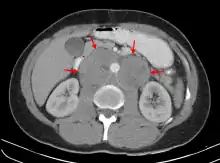

| A CT scan of axillary lymphadenopathy in a 57-year-old man with multiple myeloma. | |